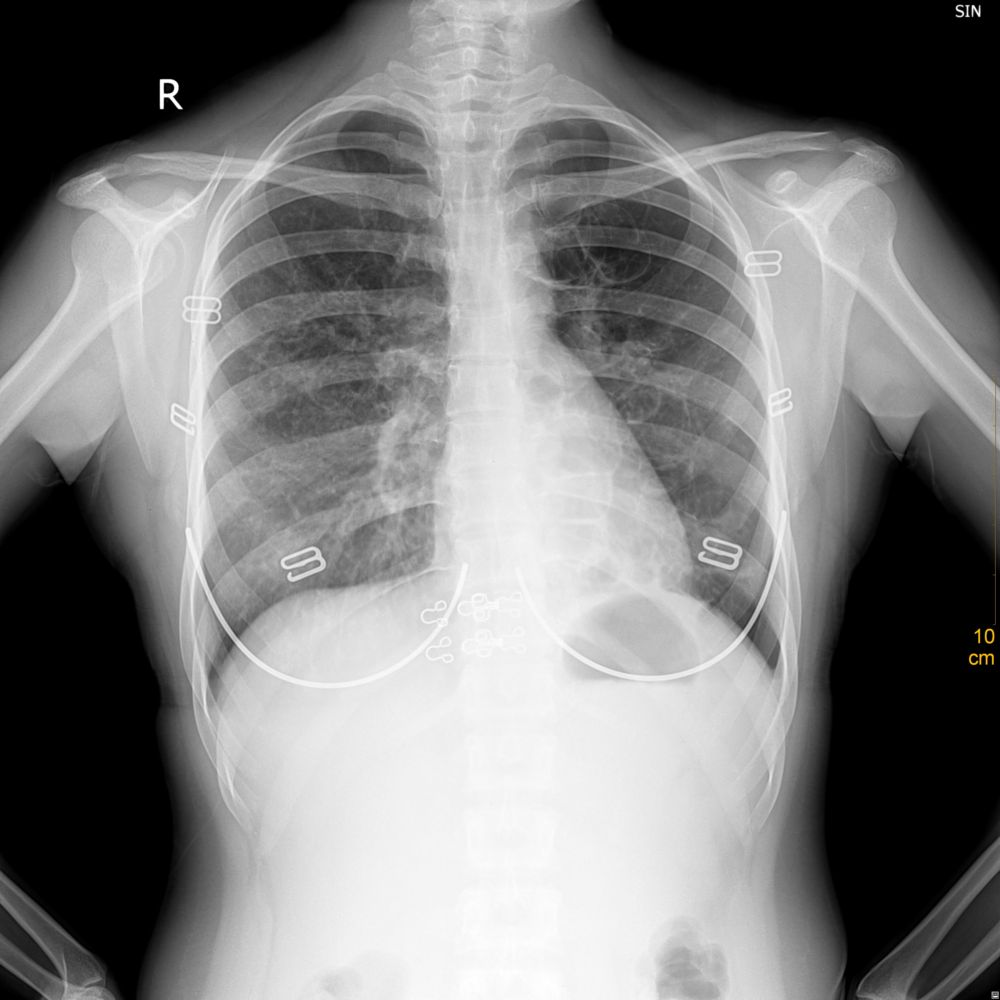

标题: X7936:女,25岁,咳嗽半月 [打印本页]

标题: X7936:女,25岁,咳嗽半月

两下肺纹理增重,尤以右侧为重,请结合临床。

左侧多囊肺。

左侧多发肺囊肿。

支气管囊肿和支扩鉴别。建议ct检查。

左肺可见多了类圆形透亮影,结合临床病史(25岁,咳嗽半月),支气管囊肿可能性比较大,建议ct。

左肺囊肿。

考虑左肺肺囊肿,双肺间质炎症。